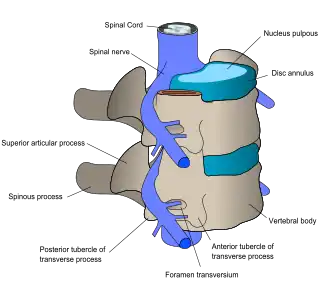

Regiunea lombară constă în cinci vertebre (L1-L5). Între acestea se află discuri fibrocartilaginoase, care acționează ca niște perne, împiedicând frecarea intervertebrală și protejând măduva spinării. Nervii vin de la și se îndreaptă către măduva spinării prin intermediul canalelor specifice dintre vertebre, dând pielii simțul tactil și trimițând mesaje mușchilor. Stabilitatea coloanei este dată de ligamentele și mușchii spatelui și abdomenului. Articulațiile mici, denumite articulații fațetare, limitează și controlează mișcarea coloanei.[12]

Un disc intervertebral are un miez gelatinos numit nucleu pulpos înconjurat de un inel fibros.[15] Când este în stare normală, neafectată, cea mai mare parte din disc nu este deservită nici de circulație, nici de sistemele nervoase – sângele și nervii ajung doar la periferia discului.[15] Celulele specializate care pot supraviețui fără o sursă directă de sânge se află în interiorul discului.[15] În timp, discurile își pierd din flexibilitate și din abilitatea de a absorbi forțele fizice.[7] Această abilitate redusă de a gestiona forțele fizice amplifică stresul aplicat altor părți din coloană, ducând la îngroșarea ligamentelor coloanei în alte regiuni ale acesteia și la dezvoltarea unor excrescențe osoase pe vertebre.[7] Prin urmare, există mai puțin spațiu prin care măduva spinării și nervii pot trece.[7] Atunci când un disc se degenerează ca urmare a rănirii sau îmbolnăvirii, aspectul acestuia se schimbă: vasele de sânge și nervii pot crește în interior și/sau materialul discului herniat poate apăsa direct pe o rădăcină nervoasă.[15] Oricare dintre aceste schimbări poate duce la apariția durerii lombare.[15]